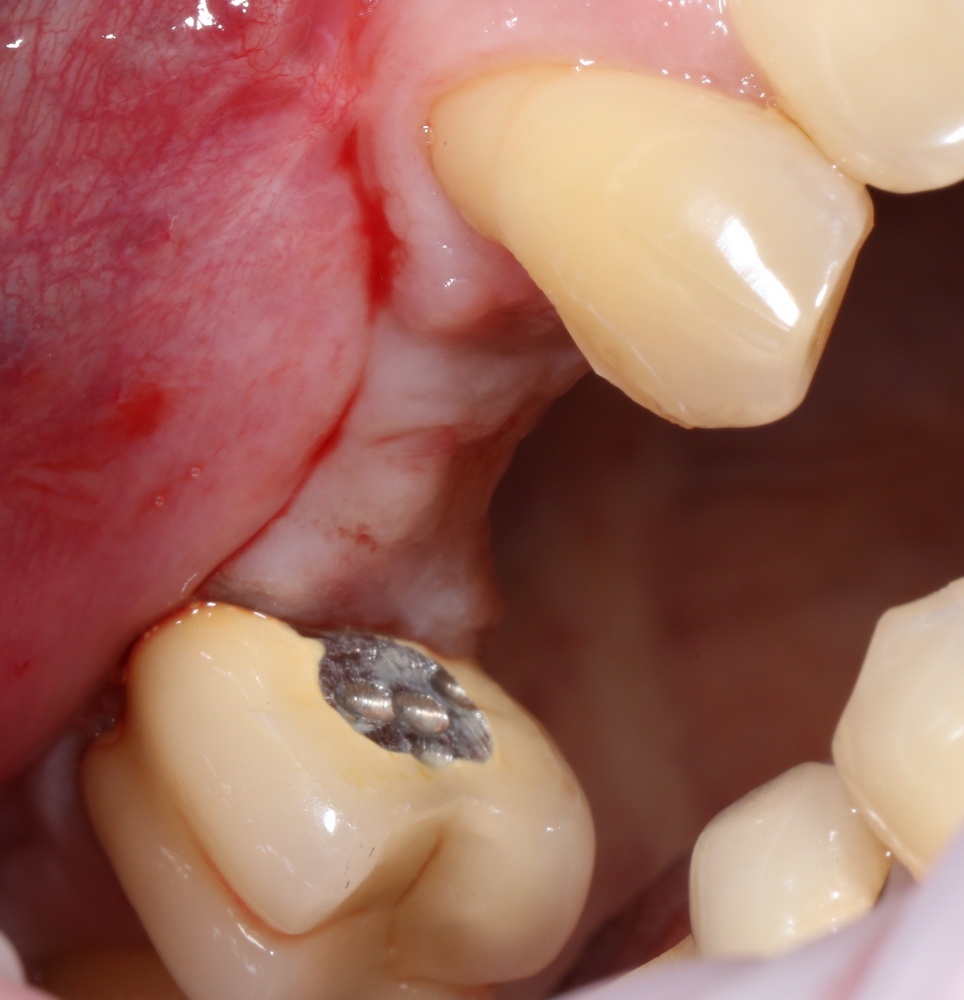

Готовимся к формированию десны. Если Вы обратили внимание, мы частично потеряли приклепленную (кератинизированную) десну, ее необходимо восстановить. Это обычное следствие остеопластических операций, особенно масштабных — почти все они требуют последующего восстановления кератинизированной слизистой оболочки.

Делаем разрез, смотрим, что там с имплантами. А с ними всё в порядке:

Как и с окружающей их костной тканью:

Обратите внимание, до какого уровня имплантат находится в костной ткани. До полированной фаски — и это правильное расположение и глубина погружения XiVE. У разных имплантационных систем они могут отличаться — см. инструкцию.

Мы ставим формирователи десны: